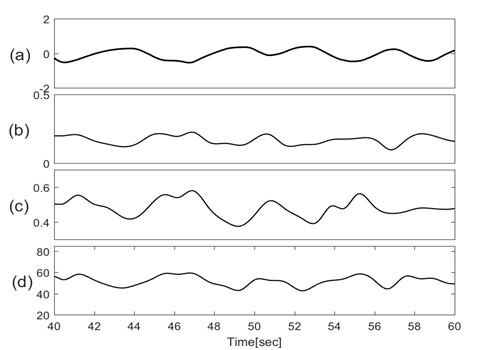

Figures 3 & 4 show the baseline wondering and amplitude modulation of SCG signals plotted along with lung volume changes that are calculated from respiratory flow measurements.

Figure 4 Traces of (a) Lung volume changes; (b) Amplitude modulation of SCG-craniocaudal; (c)Amplitude modulation of SCG-lateral; (d) Amplitude modulation of SCG-dorsoventral.